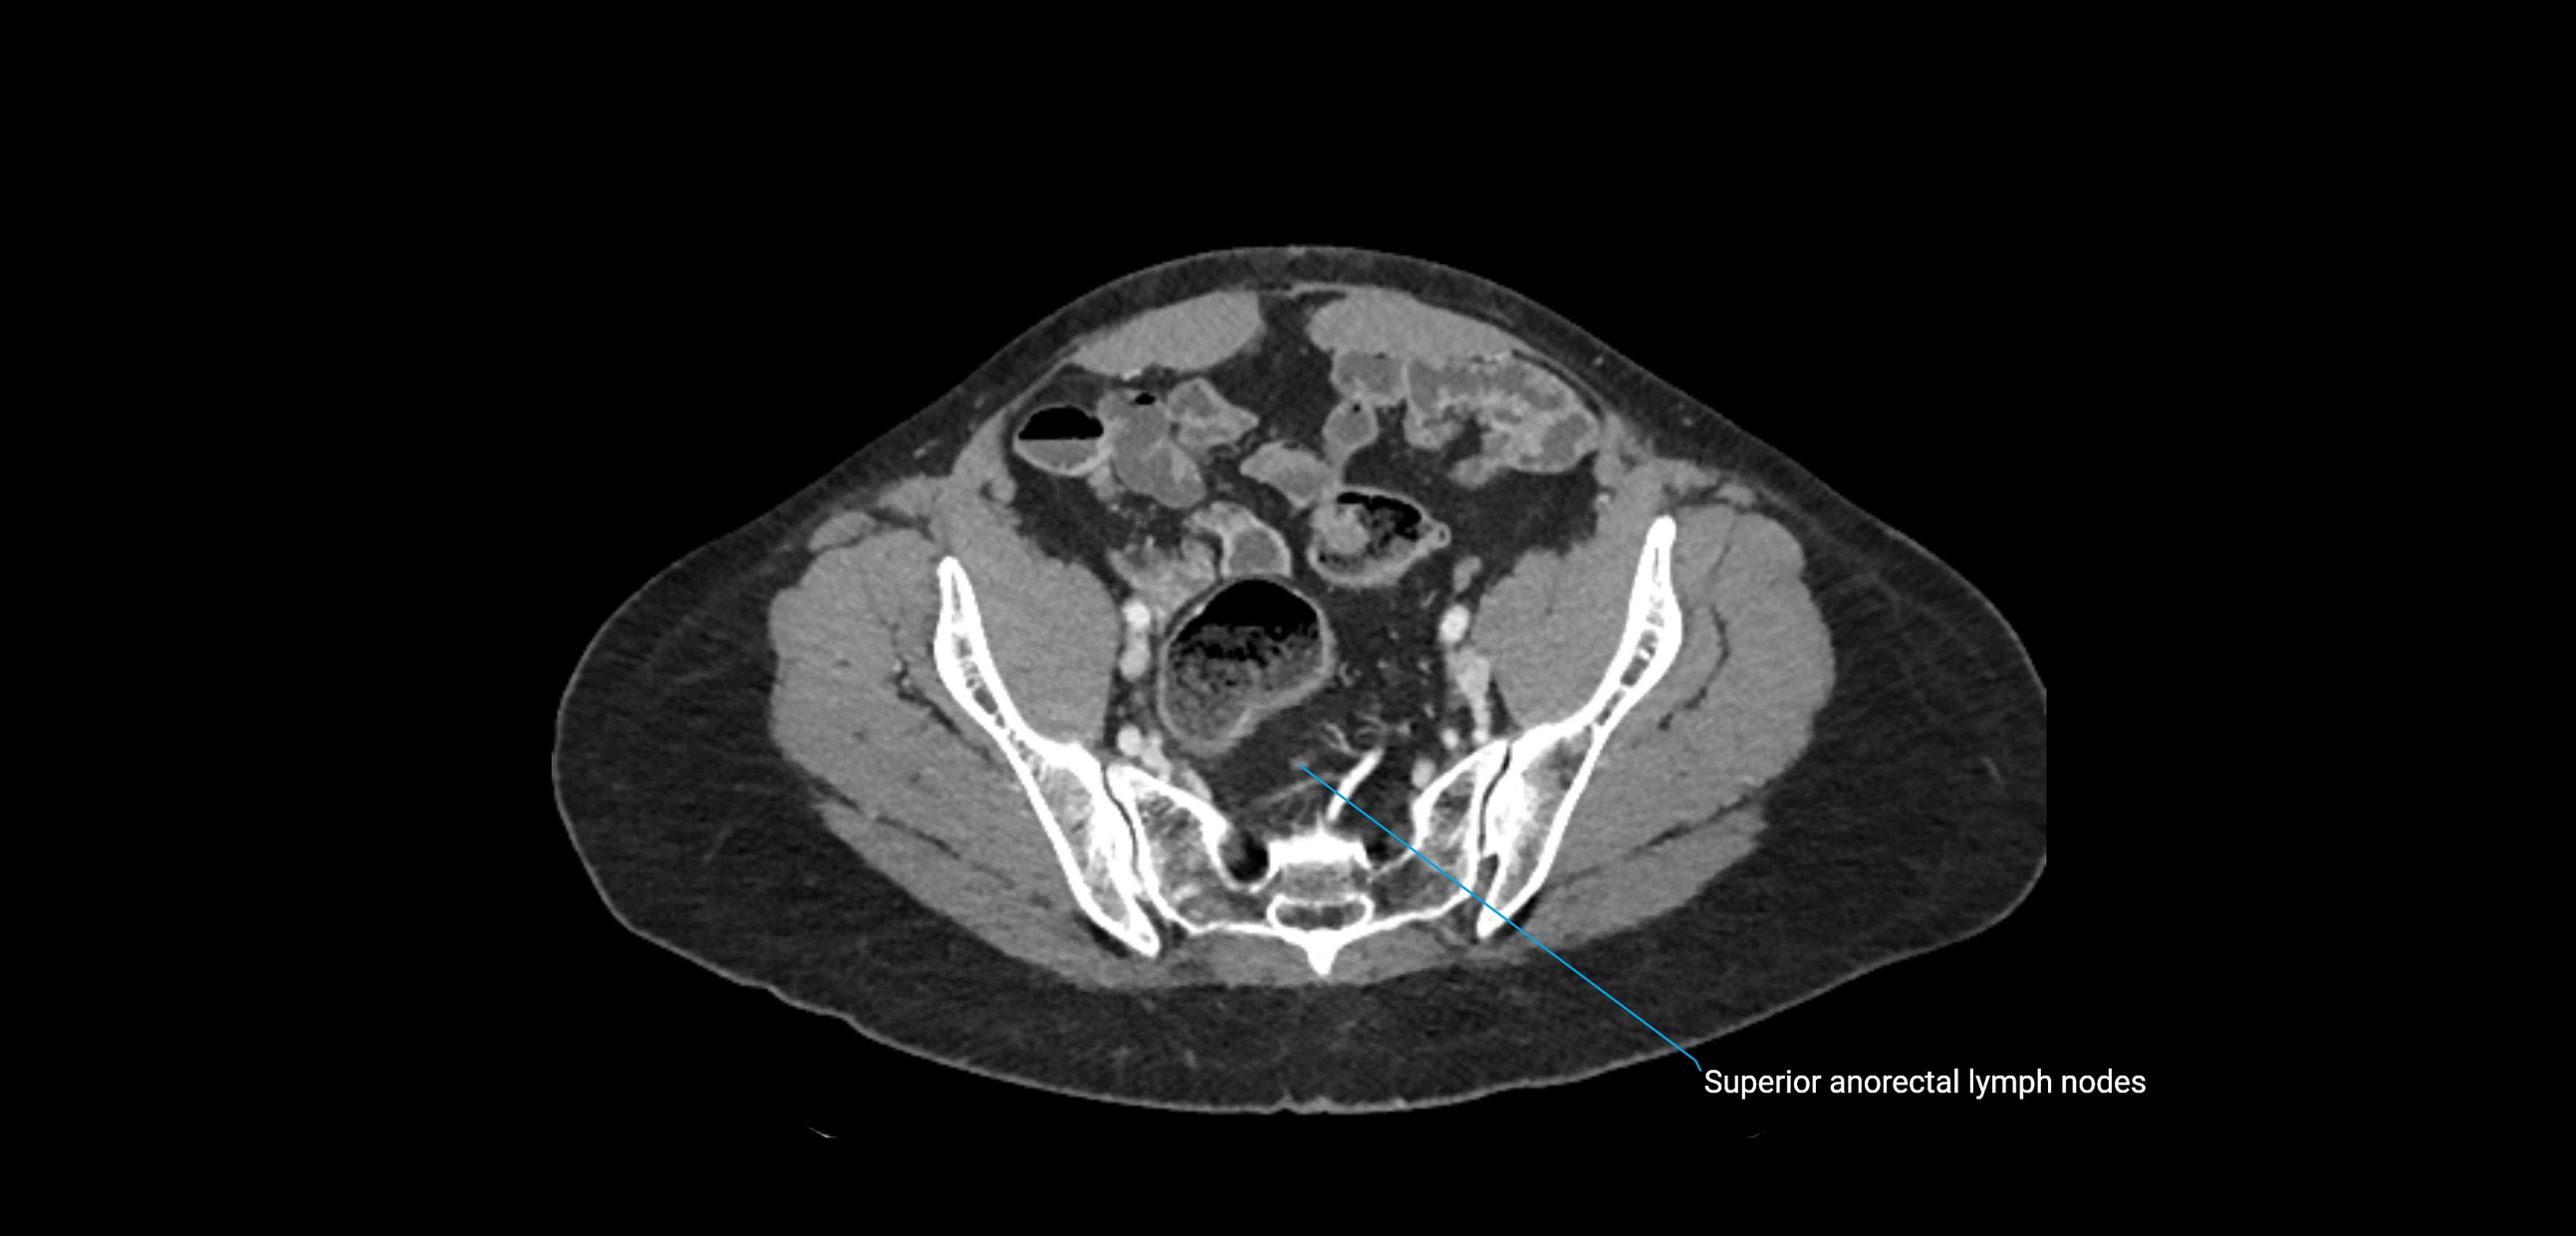

CT Appearance

CT Pre-Contrast:

• Nodes appear as soft-tissue density nodules adjacent to the aorta and IVC

• Calcification may be seen in chronic infections (e.g., tuberculosis)

CT Post-Contrast:

• Normal nodes enhance homogeneously

• Malignant nodes may show heterogeneous enhancement, central necrosis, or conglomerate formation

• Size >1 cm short axis is suspicious, though morphology and distribution are equally important